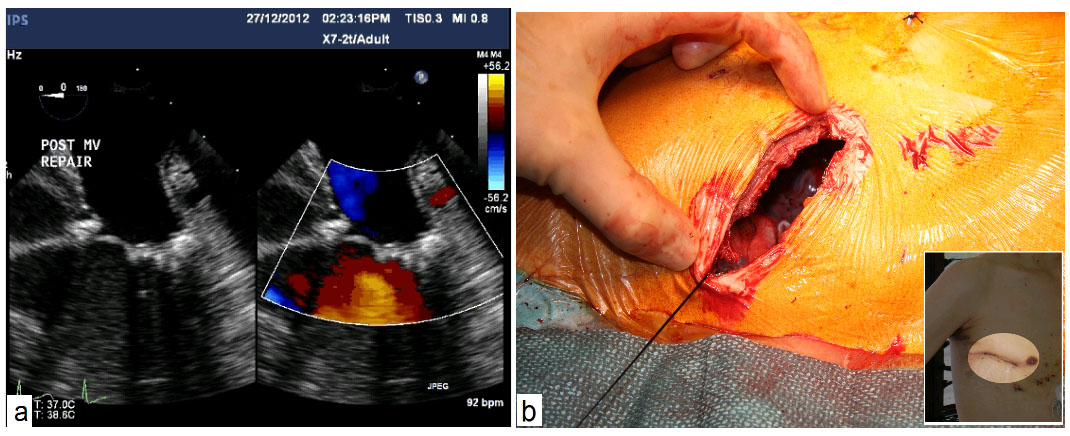

Figure 5:

Postoperative echocardiography shows good repair results (a) and a single small chest scar after surgery (b)